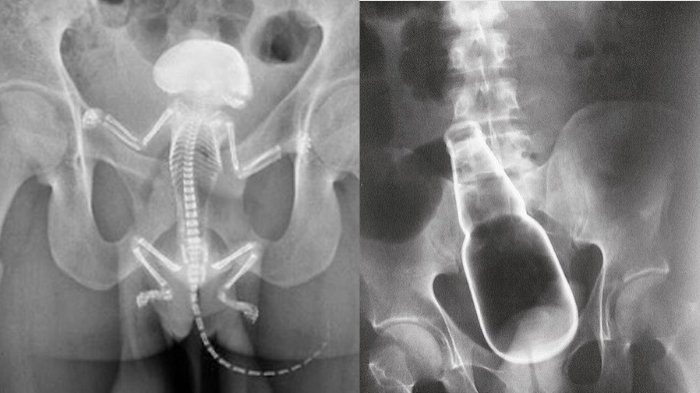

3 Benda Ini Masuk Ke Anu Pria, Yang Terakhir Punya Buntut Panjang Dan Suka Memanjat

Kasus ini pun terbilang unik dan langka, karena dokter sendiri tak habis pikir mengapa bisa terjadi.

Benda-benda ini masuk ke tubuh seseorang melalui proses yang sama sekali tak terduga.

Dilihat dari Wikipedia, rektum sendiri adalah organ terakhir dari usus besar pada beberapa jenis mamalia yang berakhir di anus.

Organ ini berfungsi sebagai tempat penyimpanan sementara feses.

Dilihat dari akun @medicaltalks, beberapa kasus di bawah ini menunjukkan benda-benda asing yang tak disangka bisa masuk ke dalam rektum.